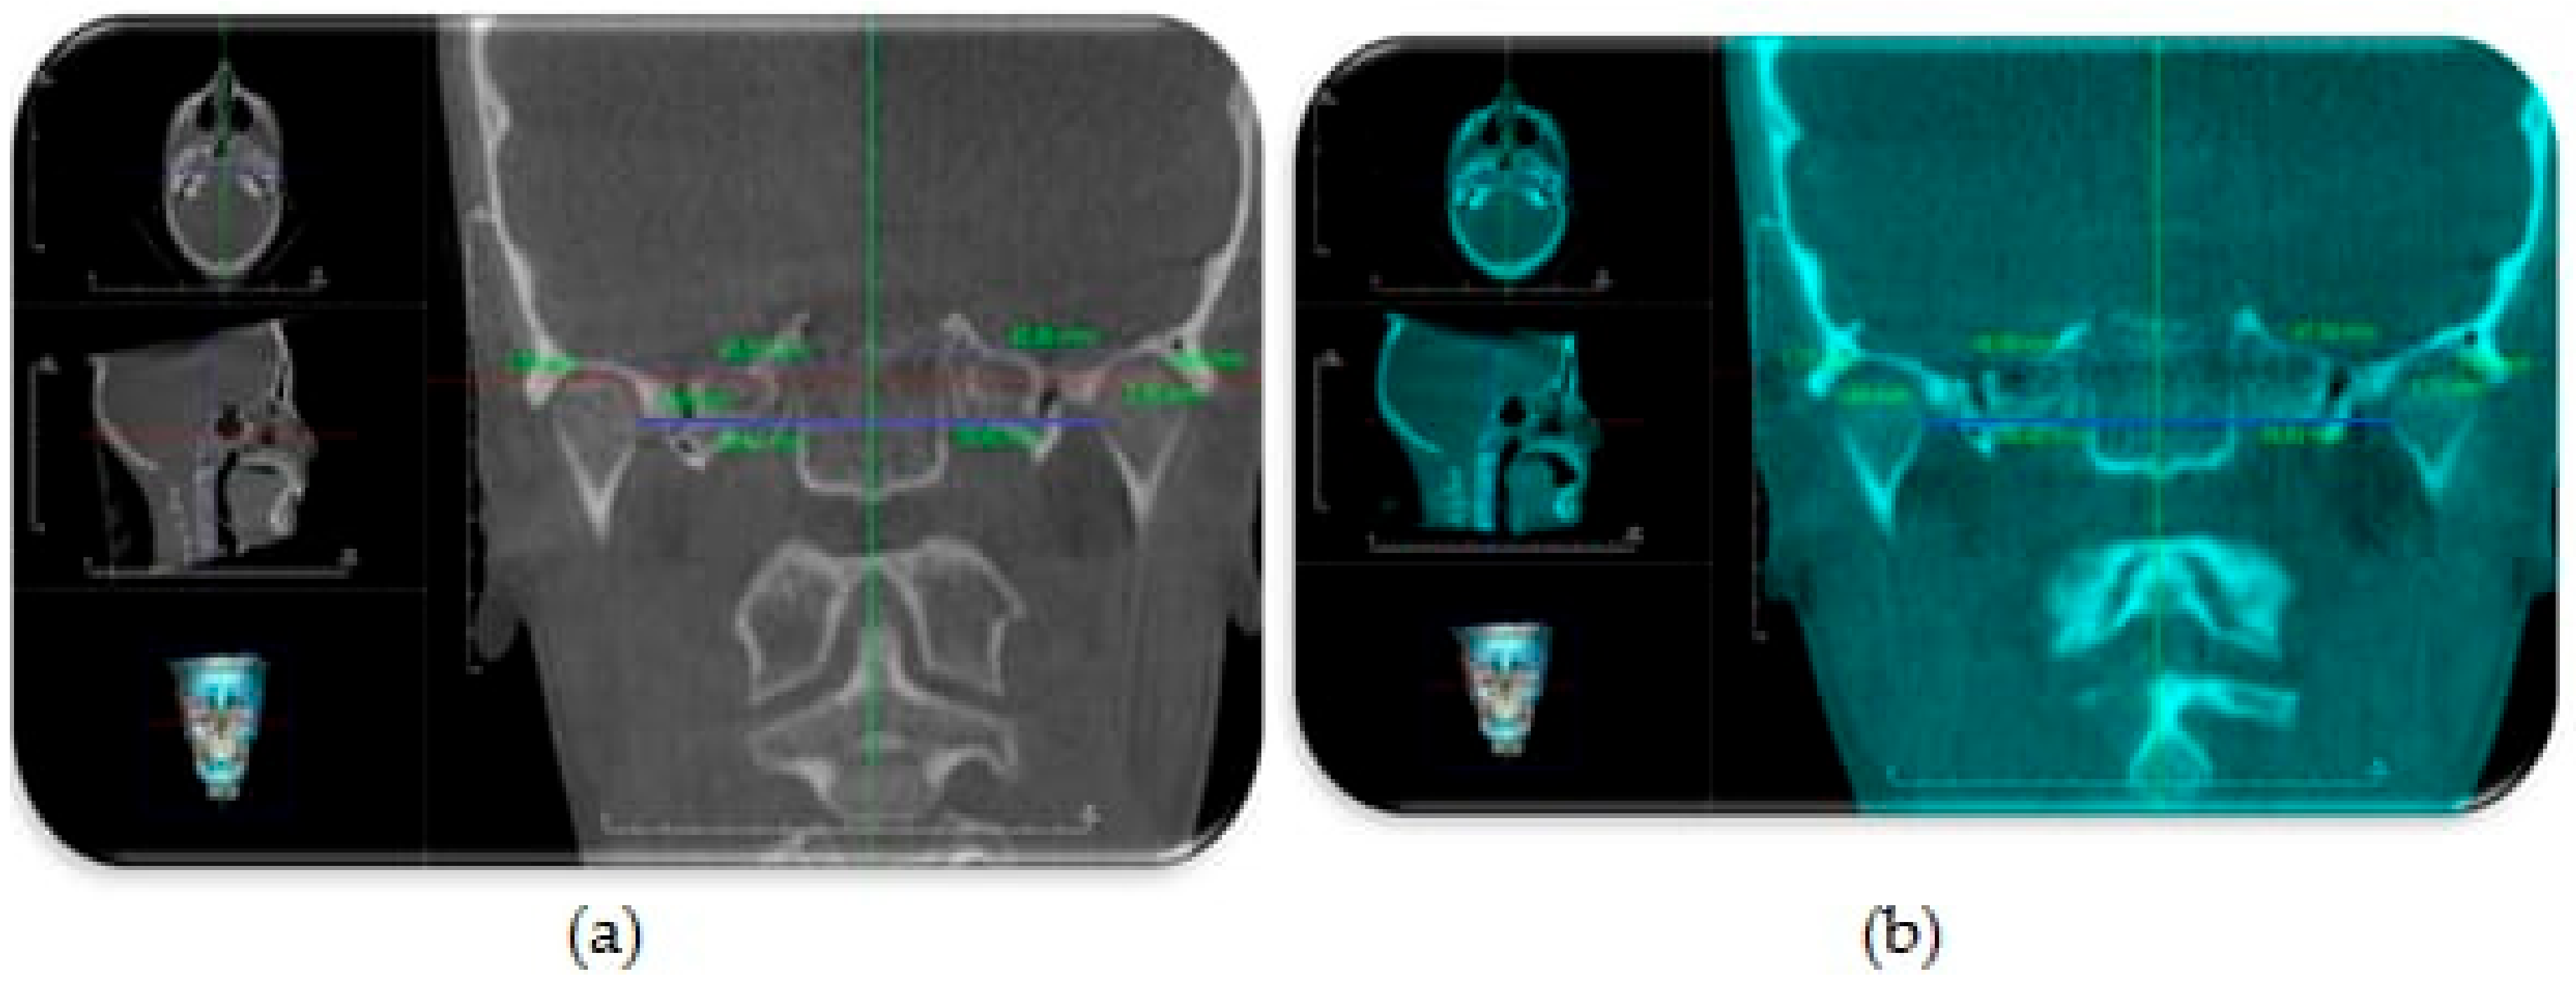

Assessment of condylar head position: The DICOM files were imported to a piece of software (Invivo Dental Anatomage; Application v 5.3.1, San Jose, CA, USA) and the orientation of each scan was rechecked and adjusted if necessary. To obtain an accurate evaluation of changes in condylar head positions between T1 and T2 images in both groups, a CBCT superimposition was made to ensure that we were referencing all measurements to the same reference planes. The three (axial, coronal and sagittal) orthogonal planes were realigned to represent the Frankfort Horizontal Plane (FHP), the Vertical Plane (VP) and midsagittal plane (MSP), respectively. From the “Superimposition” tab, the “Import New Volume” option was chosen, and DICOM files of T2 data were selected. At first, point-based registration in the midfacial region and cranial vault were employed to approximate the two scans. Next, high-precision automatic volume-based registration was utilized for the correct superimposition of T1 and T2 images (Figure 4).

The evaluation of the condylar head position was done according to the following linear measurements (Figure 5 and Figure 6) [13]:

Figure 4. Automatic volume-based registration for superimposition of T1 and T2 CBCT images utilized in the study. Orthogonal planes: axial, coronal, and sagittal aligned as reference planes for analysis of condylar head position, Vertical Plane (VP, blue line), Frankfort Horizontal Plane (FHP, red line) and midsagittal plane (MSP, green line).

Figure 5. CBCT sagittal generated view showing assessment of condylar head position relative to VP (blue line) and FHP (red line): (a) before (T1) TB therapy; (b) after TB therapy (T2).

Figure 6. CBCT coronal generated view showing assessment of condylar head position relative to MSP (green line): (a) before TB therapy; (b) after TB therapy.